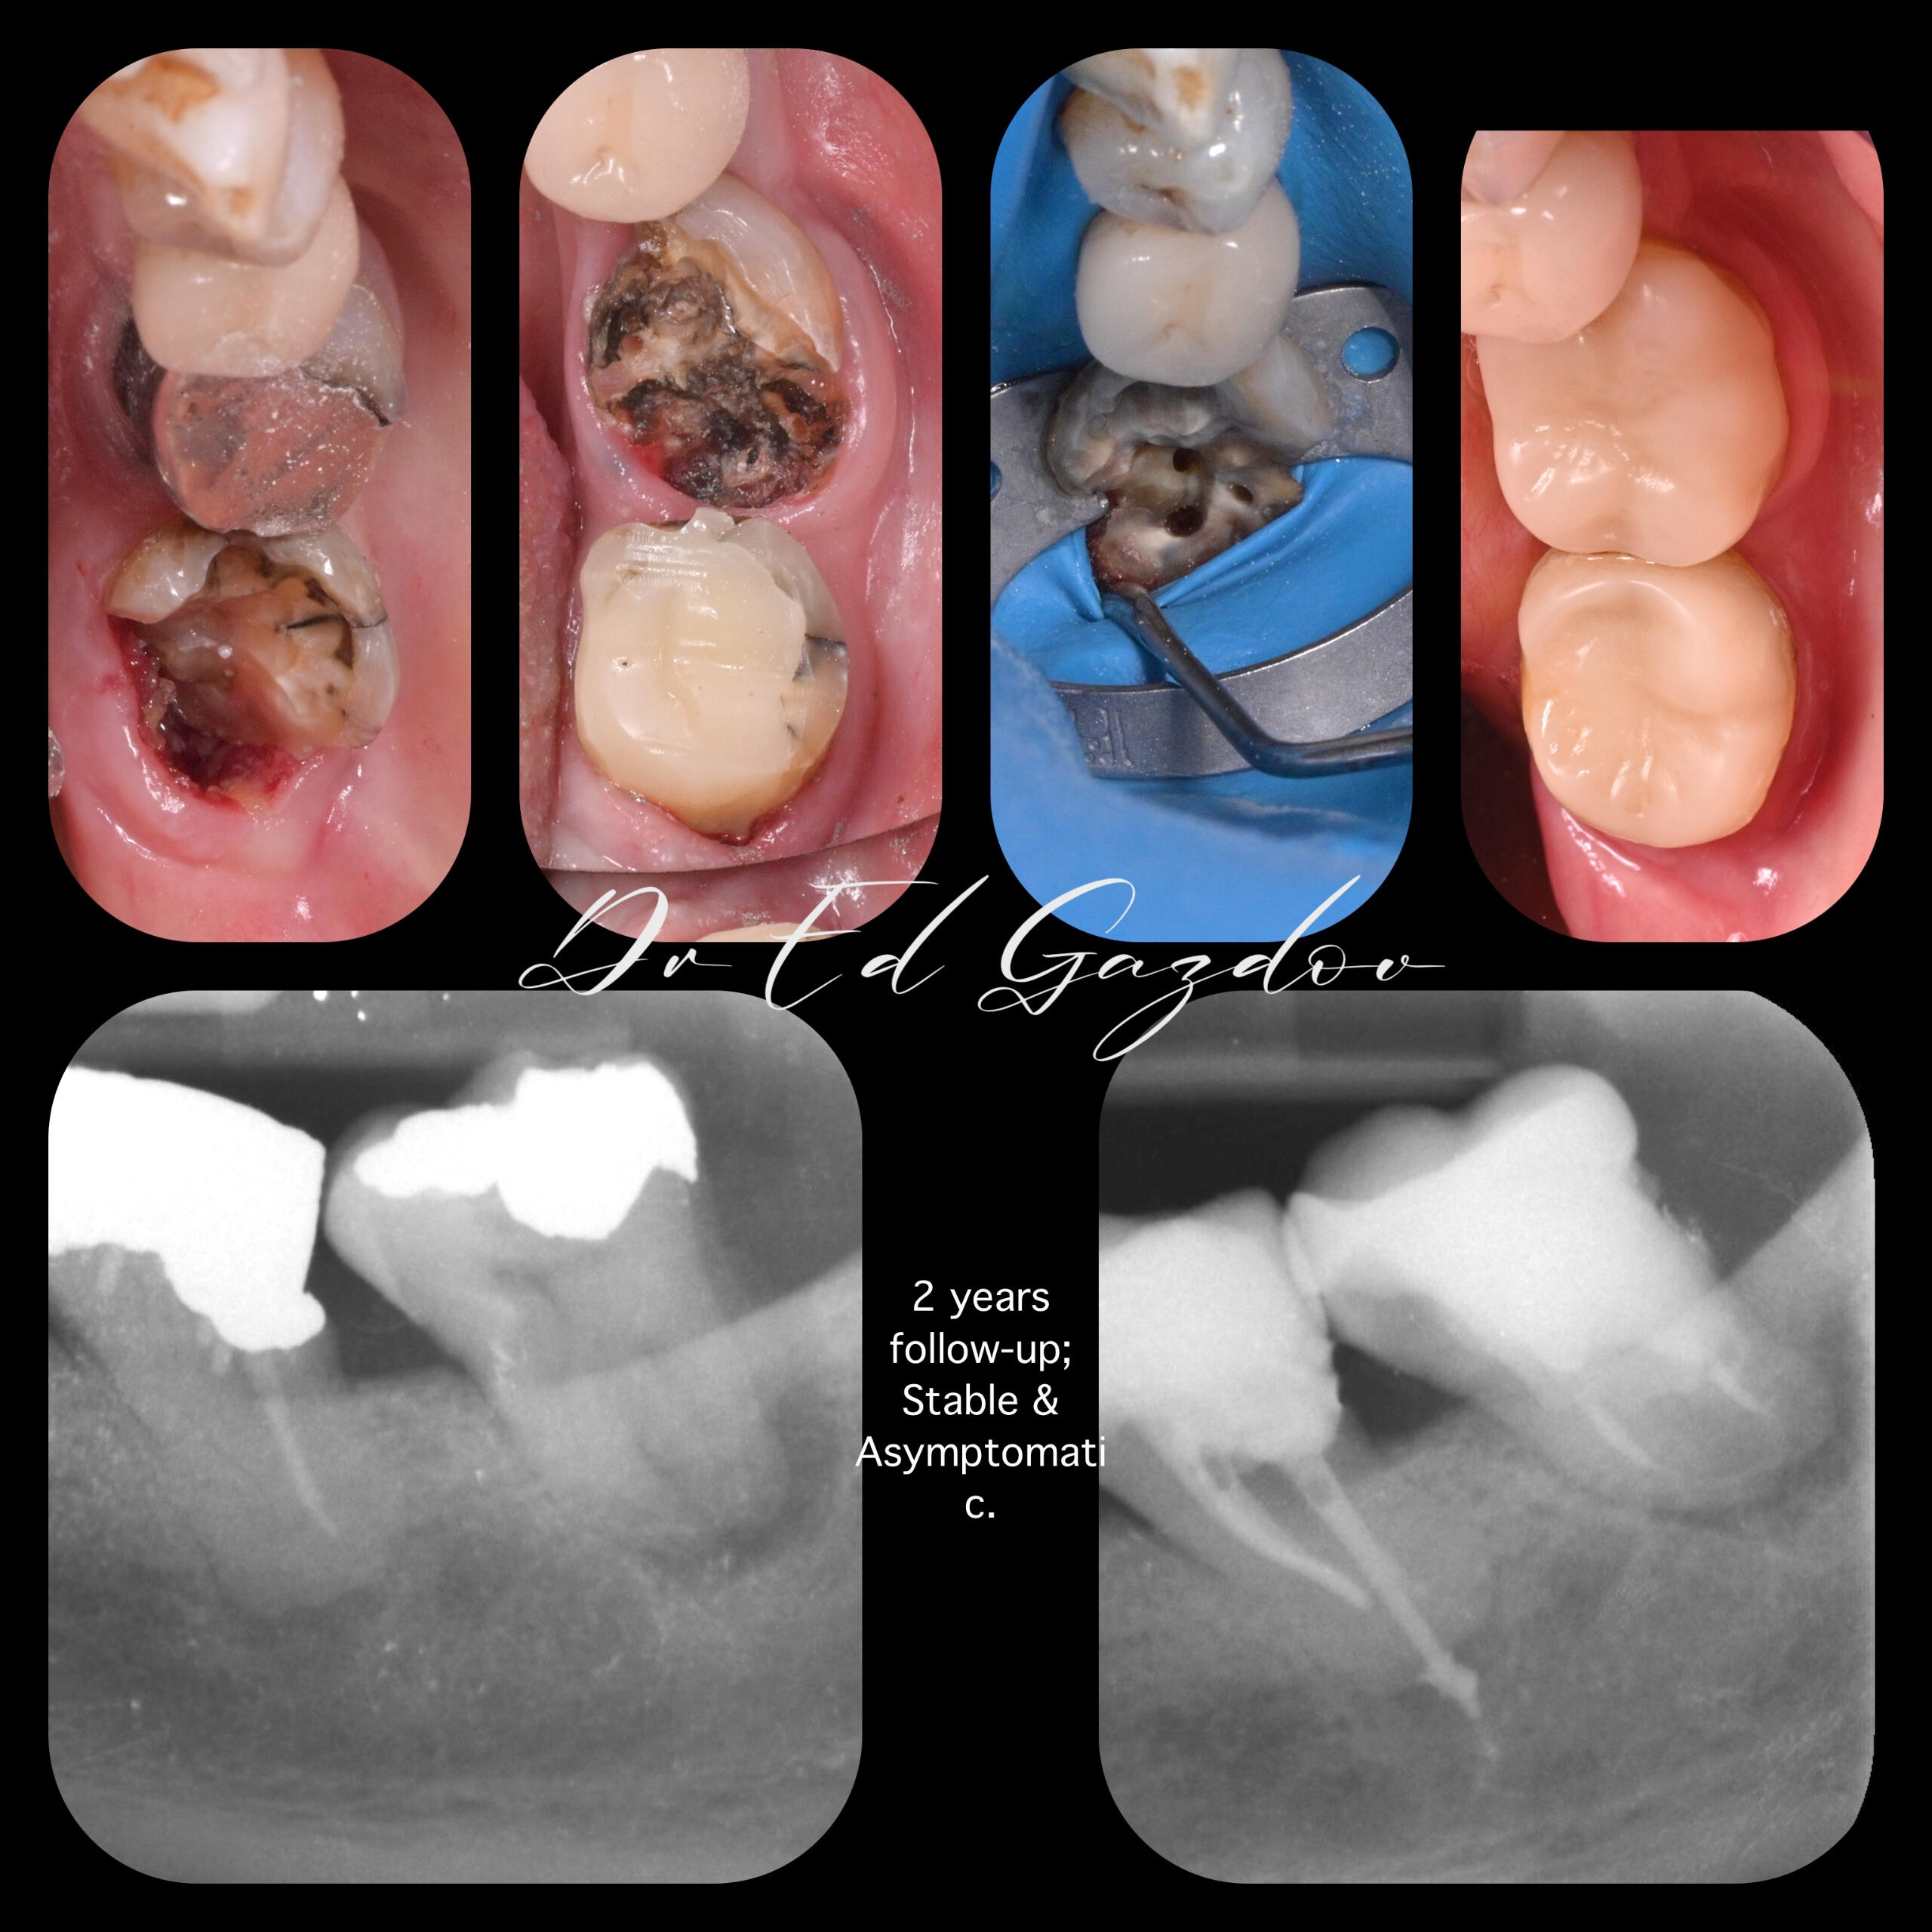

• Saving Extremely Damaged Teeth

• Complex Root Canal Treatments

BEFORE AND AFTER

Real Results. Real Patients.Every image you see here shows real treatments carried out personally by Dr. Eduard Gazdov — from start to finish.We treat complex cases using modern, evidence-based protocols. Whether it’s a full smile makeover, single-tooth restoration, or managing difficult retreatments, our approach is built on precision, communication, and care.🦷 We offer:

We work with magnification, rubber dam isolation, high-end materials and lab support, and always explain every step along the way.